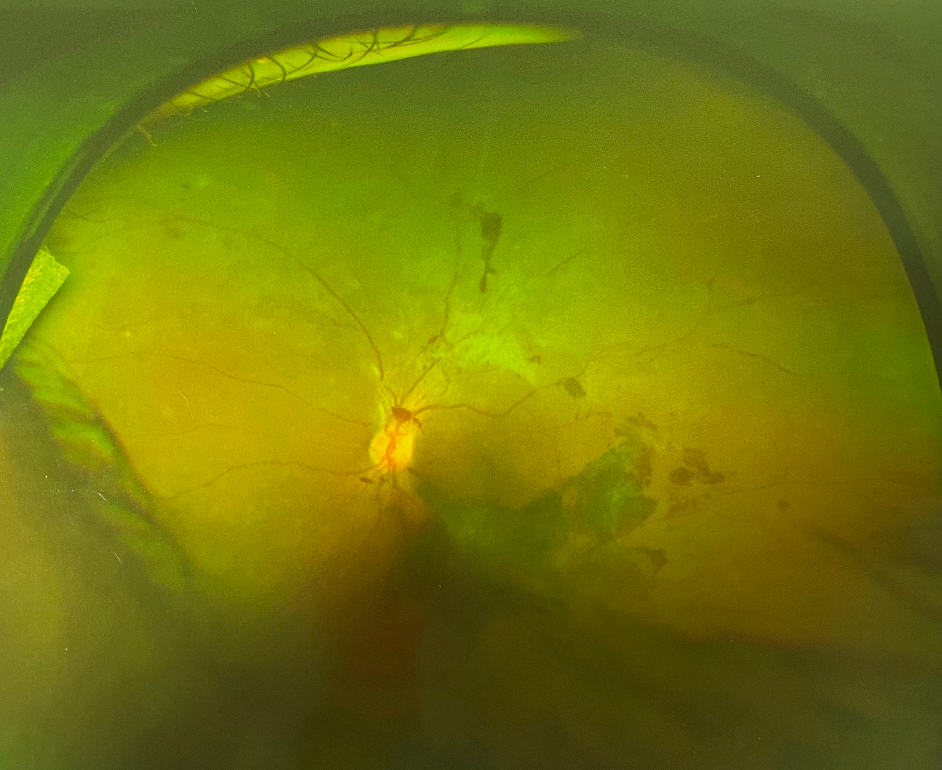

眼底出血是眼底視網(wǎng)膜血管的病變引起的。正常情況下,血液在人體的血管內(nèi)流動(dòng),不會(huì)溢出,但如果身體出了問題,無論是眼睛局部的問題還是全身的病變,在眼睛血管里流動(dòng)的血液就會(huì)溢出來,溢在視網(wǎng)膜上,這就形成了眼底出血。那么眼底出血的癥狀有哪些呢?

由于眼底出血的原因及部位不同,預(yù)后及對(duì)患者視力的影響也不一樣,依照出血量的多少,出血部位不同而產(chǎn)生不同的癥狀。如出血量少,位于視乳頭及視網(wǎng)膜周邊部,可以沒有明顯眼底出血的癥狀,如出血量多,患者感到眼前有黑影浮動(dòng),視線被部分或完全遮擋,僅剩光感的視力。如出血位于視網(wǎng)膜中心(黃斑區(qū))患者中心視力喪失,即中心區(qū)視物不清有暗影遮擋,周邊尚有部分視力。